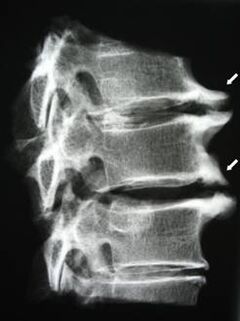

საწყის ეტაპზე ოსტეოქონდროზის გამოვლენა ხდება MRI-ს გამოყენებით. მოგვიანებით, პათოლოგიის დიაგნოსტირება შესაძლებელია რენტგენოგრაფიის გამოყენებით. საშვილოსნოს ყელის ხერხემლის რენტგენოგრაფიაზე შესამჩნევი ხდება ხერხემლიანებს შორის მანძილის დაქვეითება, ფაზის სახსრების პათოლოგიური ცვლილებები და ოსტეოფიტოზი.